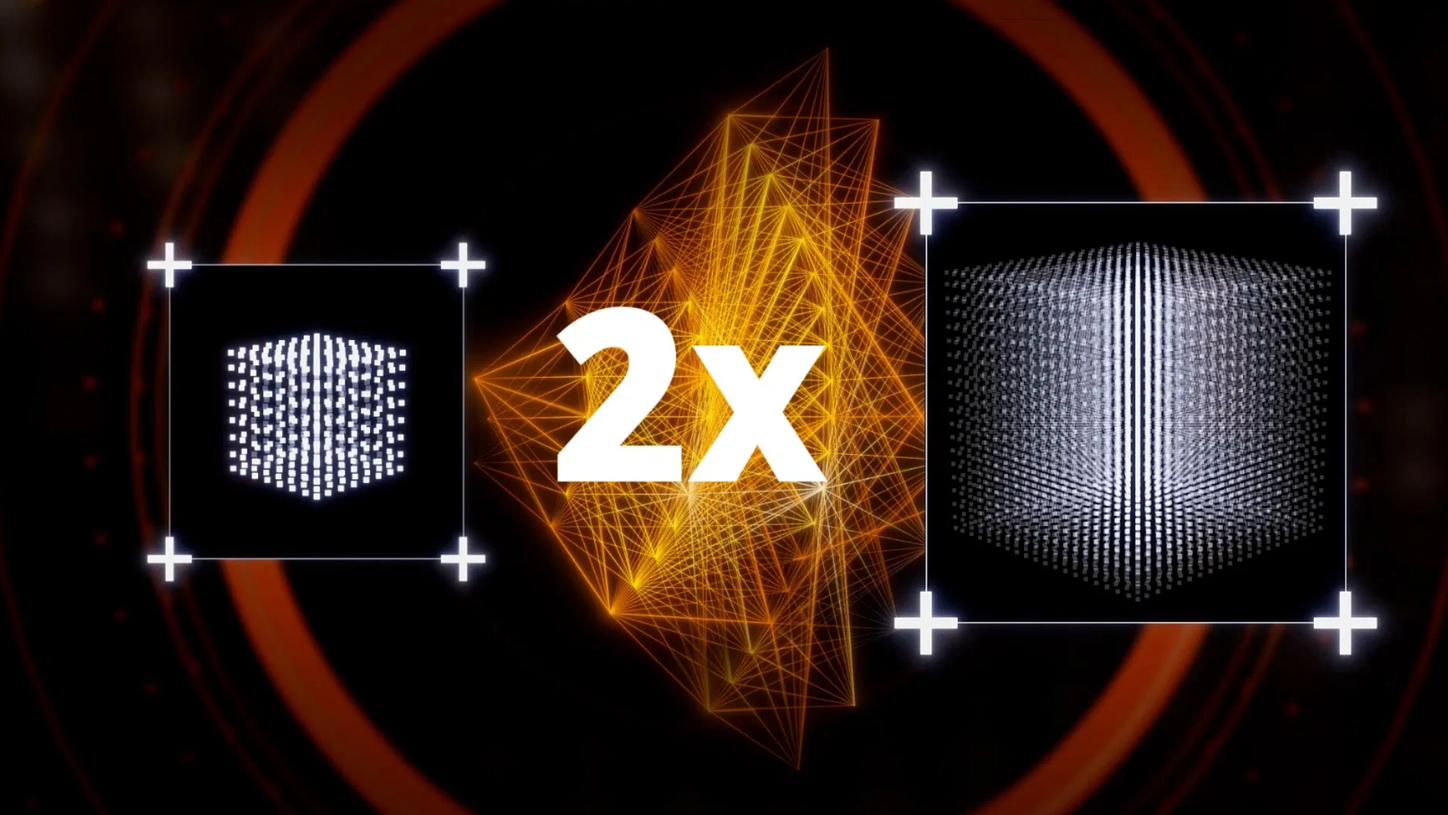

We are empowering decision making for technologists, radiologists, and clinicians along the whole imaging value chain and making it even smarter – allowing healthcare professionals to make the right decision at the right time within the patient pathway. Our AI-powered solutions are not just tools but essential allies in the modern medical imaging landscape, designed to increase productivity, improve clinical precision, and be integrated seamlessly.

By accelerating data analysis and image acquisition

With advanced algorithms